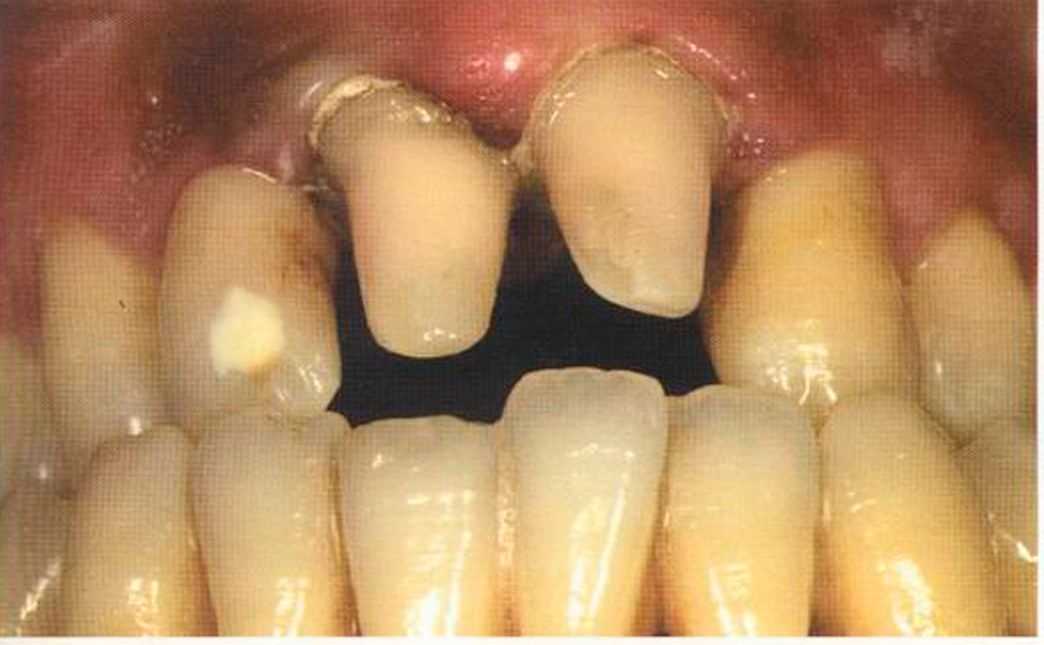

Этот пациент — португалец. Он всю жизнь имел такое положение зубов. Небнорасположенный боковой резец теперь необходимо удалить, а затем воссоздать как эстетику, так и функцию в области фронтальной группы зубов. Планируется изготовить коронки In-Ceram в области 11 и 21 и соединить их вместе из-за увеличивающейся подвижности зубов.

Препарирование, проводимое доктором Риссе, оценивается как очень сложное. Режущие края центральных резцов сильно дивергируют, что создает неудобство при формировании хорошего уступа.

Из-за сильной протрузии центральных резцов на них всегда падает итого света, и они кажутся очень большими. Чтобы смягчить этот эффект, мы выбрали более темный цвет для реставрации.

Фото сверху и слева: отличный результат препарирования зубов с уже уложенными нитями для снятия оттиска.

Готовая работа привела в восторг нашего пациента. Он даже не мог себе представить, что соединенные вместе коронки могут выглядеть так естественно. Мы решили не копировать на реставрацию белое пятно, имеющееся на 12 зубе.